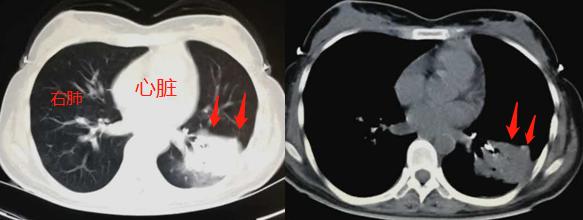

CT片显示:左下肺大片实变影(白色),形态不规则,边缘模糊,近端支气管狭窄。

老主任在看片子之前,先做了放大和拆薄处理,之后盯着片子看了十多秒钟,指着这里说了5个字:

支气管异物!

咦?病变近端支气管内有一小块白色的高密度影,这不是钙化?是气管内异物?